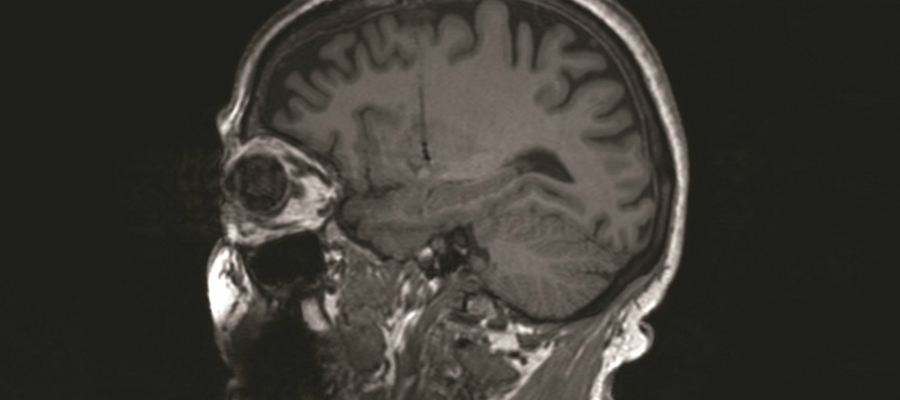

De varkenscellen zijn afkomstig uit de plexus choroideus van varkens. Dit hersengebiedje maakt hersenvocht: een cocktail van groeifactoren en signaalmoleculen die zenuwcellen gezond houdt. Het idee is dat de plexus-choroideus-cellen van een varken de overgebleven dopamine-producerende cellen van parkinsonpatiënten ‘smeert’ en zo verder verlies zo goed als mogelijk helpt voorkomen.